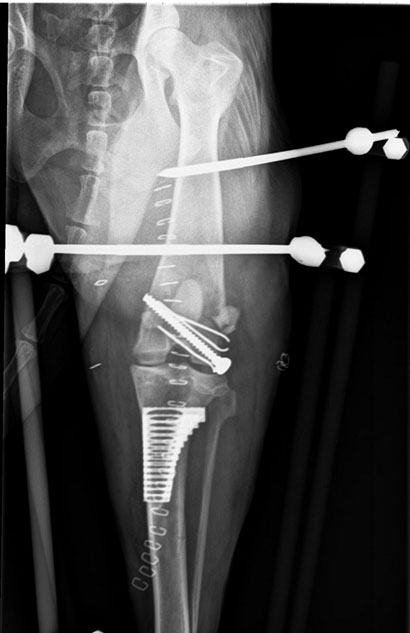

Da ihr Knie nach wie vor sehr instabil war, musste sie nochmals an den hinteren Kreuzbändern operiert werden.

Weiterhin werden wir jetzt versuchen, dass Knie mit gezieltem Muskelaufbau zu stabilisieren.

Dezember 2017

Auch der lästige Fixateur wurde inzwischen entfernt.

Dennoch- Ihre Klinikodysse ist noch nicht zu Ende.

Das Knie wurde, als man Laika überfuhr, stark geschädigt und es wird noch einiges Zeit in Anspruch nehmen bis es wieder richtig funktioniern wird.

Als nächste Operation steht das Kreuzband an. Anschliessend wird noch in der Klinik damit begonnen durch Bewegungstherapien Laikas Muskulatur zu stabiliseren.

Die Hündin irrte alleine umher und wurde in der Folge von einem Auto angefahren und schwerst-verletzt.

So wurde sie daraufhin in ihrem schrecklichen Zustand an das SPA übergeben, dieses hat zum Glück schnell reagiert und so konnte die hübsche, äußerst liebe Maus auf ihre Schutzengel zählen: Laikas ganzer Körper, die Beine, das Auge ist mit Schürfwunden und Prellungen übersät.

Wenn auch mit einem sprichwörtlichen Totalschaden an einem der Hinterbeine.

Der lieben Laika konnte in einer aufwendigen Operation geholfen werden und die schönste Nachricht ist, dass Laika nach ihrer Genesung wieder rennen darf, darauf freuen wir uns schon jetzt sehr!!